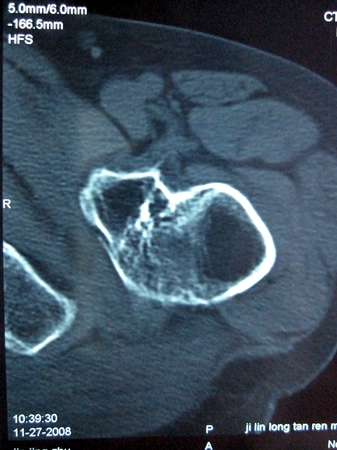

以下是引用lkc8963在2008-12-19 21:19:00的发言:[br]左?右?患侧大转子上移,股骨颈骨质浓杂,髋周见多发条片状骨化影,以小转子为著,多为陈旧性股骨颈骨折后改变并骨化性肌炎.请咨询既往史!